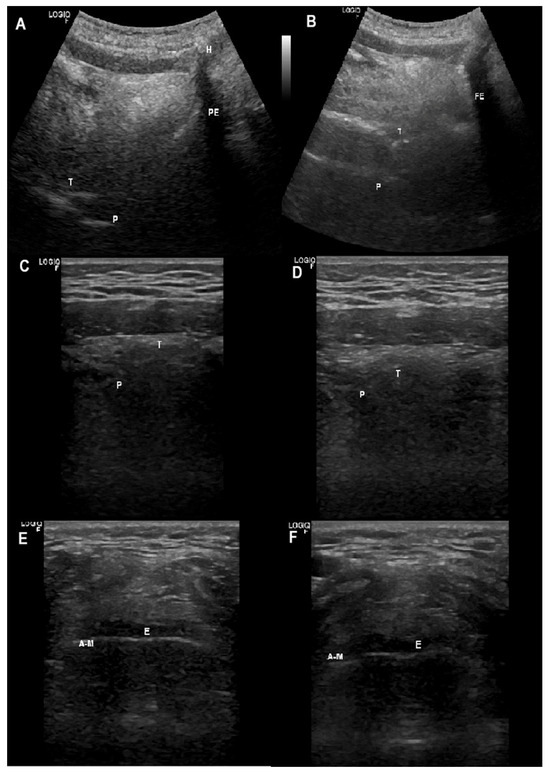

2.7.1. Ultrasonographic Upper Airway Structures

Supra-Glottis

Oropharynx

- Brekka, A.K.; Vollsaeter, M.; Ntoumenopoulos, G.; Clemm, H.H.; Halvorsen, T.; Roksund, O.D.; Andersen, T.M. Adjustments of non-invasive ventilation and mechanically assisted cough by combining ultrasound imaging of the larynx with transnasal fibre-optic laryngoscopy: A protocol for an experimental study. BMJ Open 2022, 12, e059234. [Google Scholar] [CrossRef]